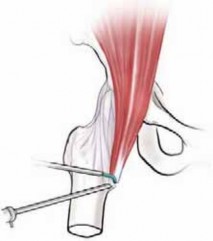

ENDOSCOPIC ILIOPSOAS RELEASE Lesser Trochanter (Iliopsoas Bursa)

1. After completing routine hip arthroscopy, including intra-articular and peripheral compartments, the leg is repositioned in 20 degrees of flexion and full external rotation.

2. Slight flexion partially relaxes the tendon but maintains some tension.

3. External rotation brings the lesser trochanter more anterior for access from the laterally based portals (

TECH FIG 1A

).

4. A portal is established distal to the standard anterolat-eral hip portal at the level of the lesser trochanter, using fluoroscopic guidance (

TECH FIG 1B

1. This exposes the tendon within the iliopsoas bursa, which is the largest bursa in the body.

5. Another portal is then placed distally, converging toward the lesser trochanter (

TECH FIG 1C

6. The arthroscope and instruments are switched between these two portals for thorough visualization and instrumentation of the iliopsoas tendon (

TECH FIG 1D

TECH FIG 1•

Release of right iliopsoas tendon from lesser trochanter.

A.

The hip is flexed approximately 20 degrees and externally rotated.

B.

Initial portal established at level of lesser trochanter. C. Ancillary portal is established distally under direct arthroscopic visualization. D. The arthroscope has been switched to the more distal portal with a flexible radiofrequency (RF) device introduced proximally. E. Arthroscopic illustration shows release of the tendinous portion of the iliopsoas. (Courtesy of J. W.

E Thomas Byrd, MD.)